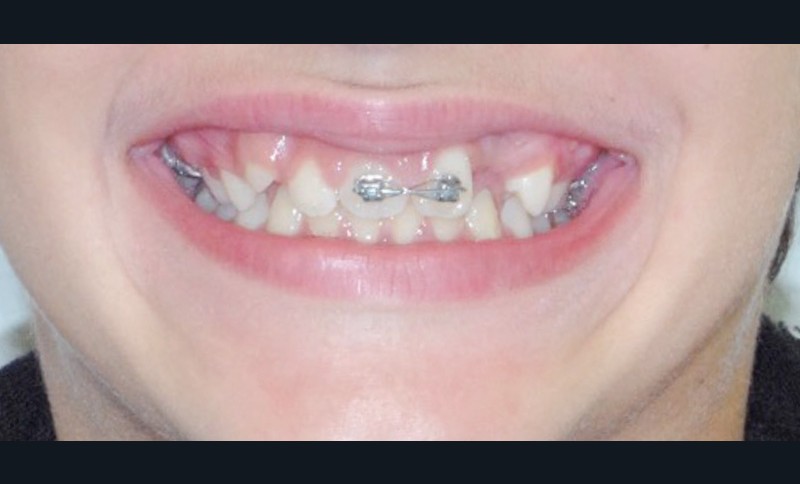

Le jeune Yoan 9 ans est adressé par son chirurgien maxillofacial, suite à l’exérèse d’un kyste bénin du maxillaire, et l’avulsion de 21 et 23 (fig. 1). L’apex de 22 a été soufflé par le kyste. La céphalométrie (fig. 2a et b) et l’examen clinique mettent en évidence une classe II squelettique par rétromandibulie, ainsi qu’une classe II dentaire. Le patient, est particulièrement perturbé par l’intervention qu’il vient de subir, et la coopération s’annonce difficile.